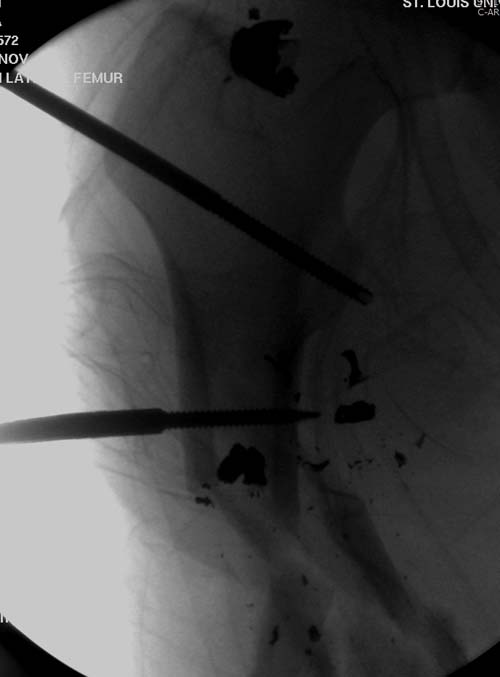

На снимках осложнение огнестрельного перелома бедра поздней инфекцией. 7 лет назад оперирован: правое бедро, сперва на ExFix, затем заменен на гвоздь, а левая - гвоздь при поступлении.

Беспокойство проявил недавно, по поводу жалоб на боли сделано МРТ и дренирование абсцесса терапевтами. Мы удалили гвоздь, сделали I&D, рассверливание канала, и ввели гвоздь с антибиотиком. Для гвоздя использовали стерильную трубку-форму, а антибиотик по 1.0 Tobramycin c Vancomycin.

В замкнутом без перелома пространстве во время риминга повышается давление внутри канала, и имеется риск тромбообразования. Для профилактики и для дренажа - каннюлированный винт 6.5 мм в дистальной части бедра. Обработку заканчивают культурой из раны и канала. Иногда процедуру надо будет повторить.